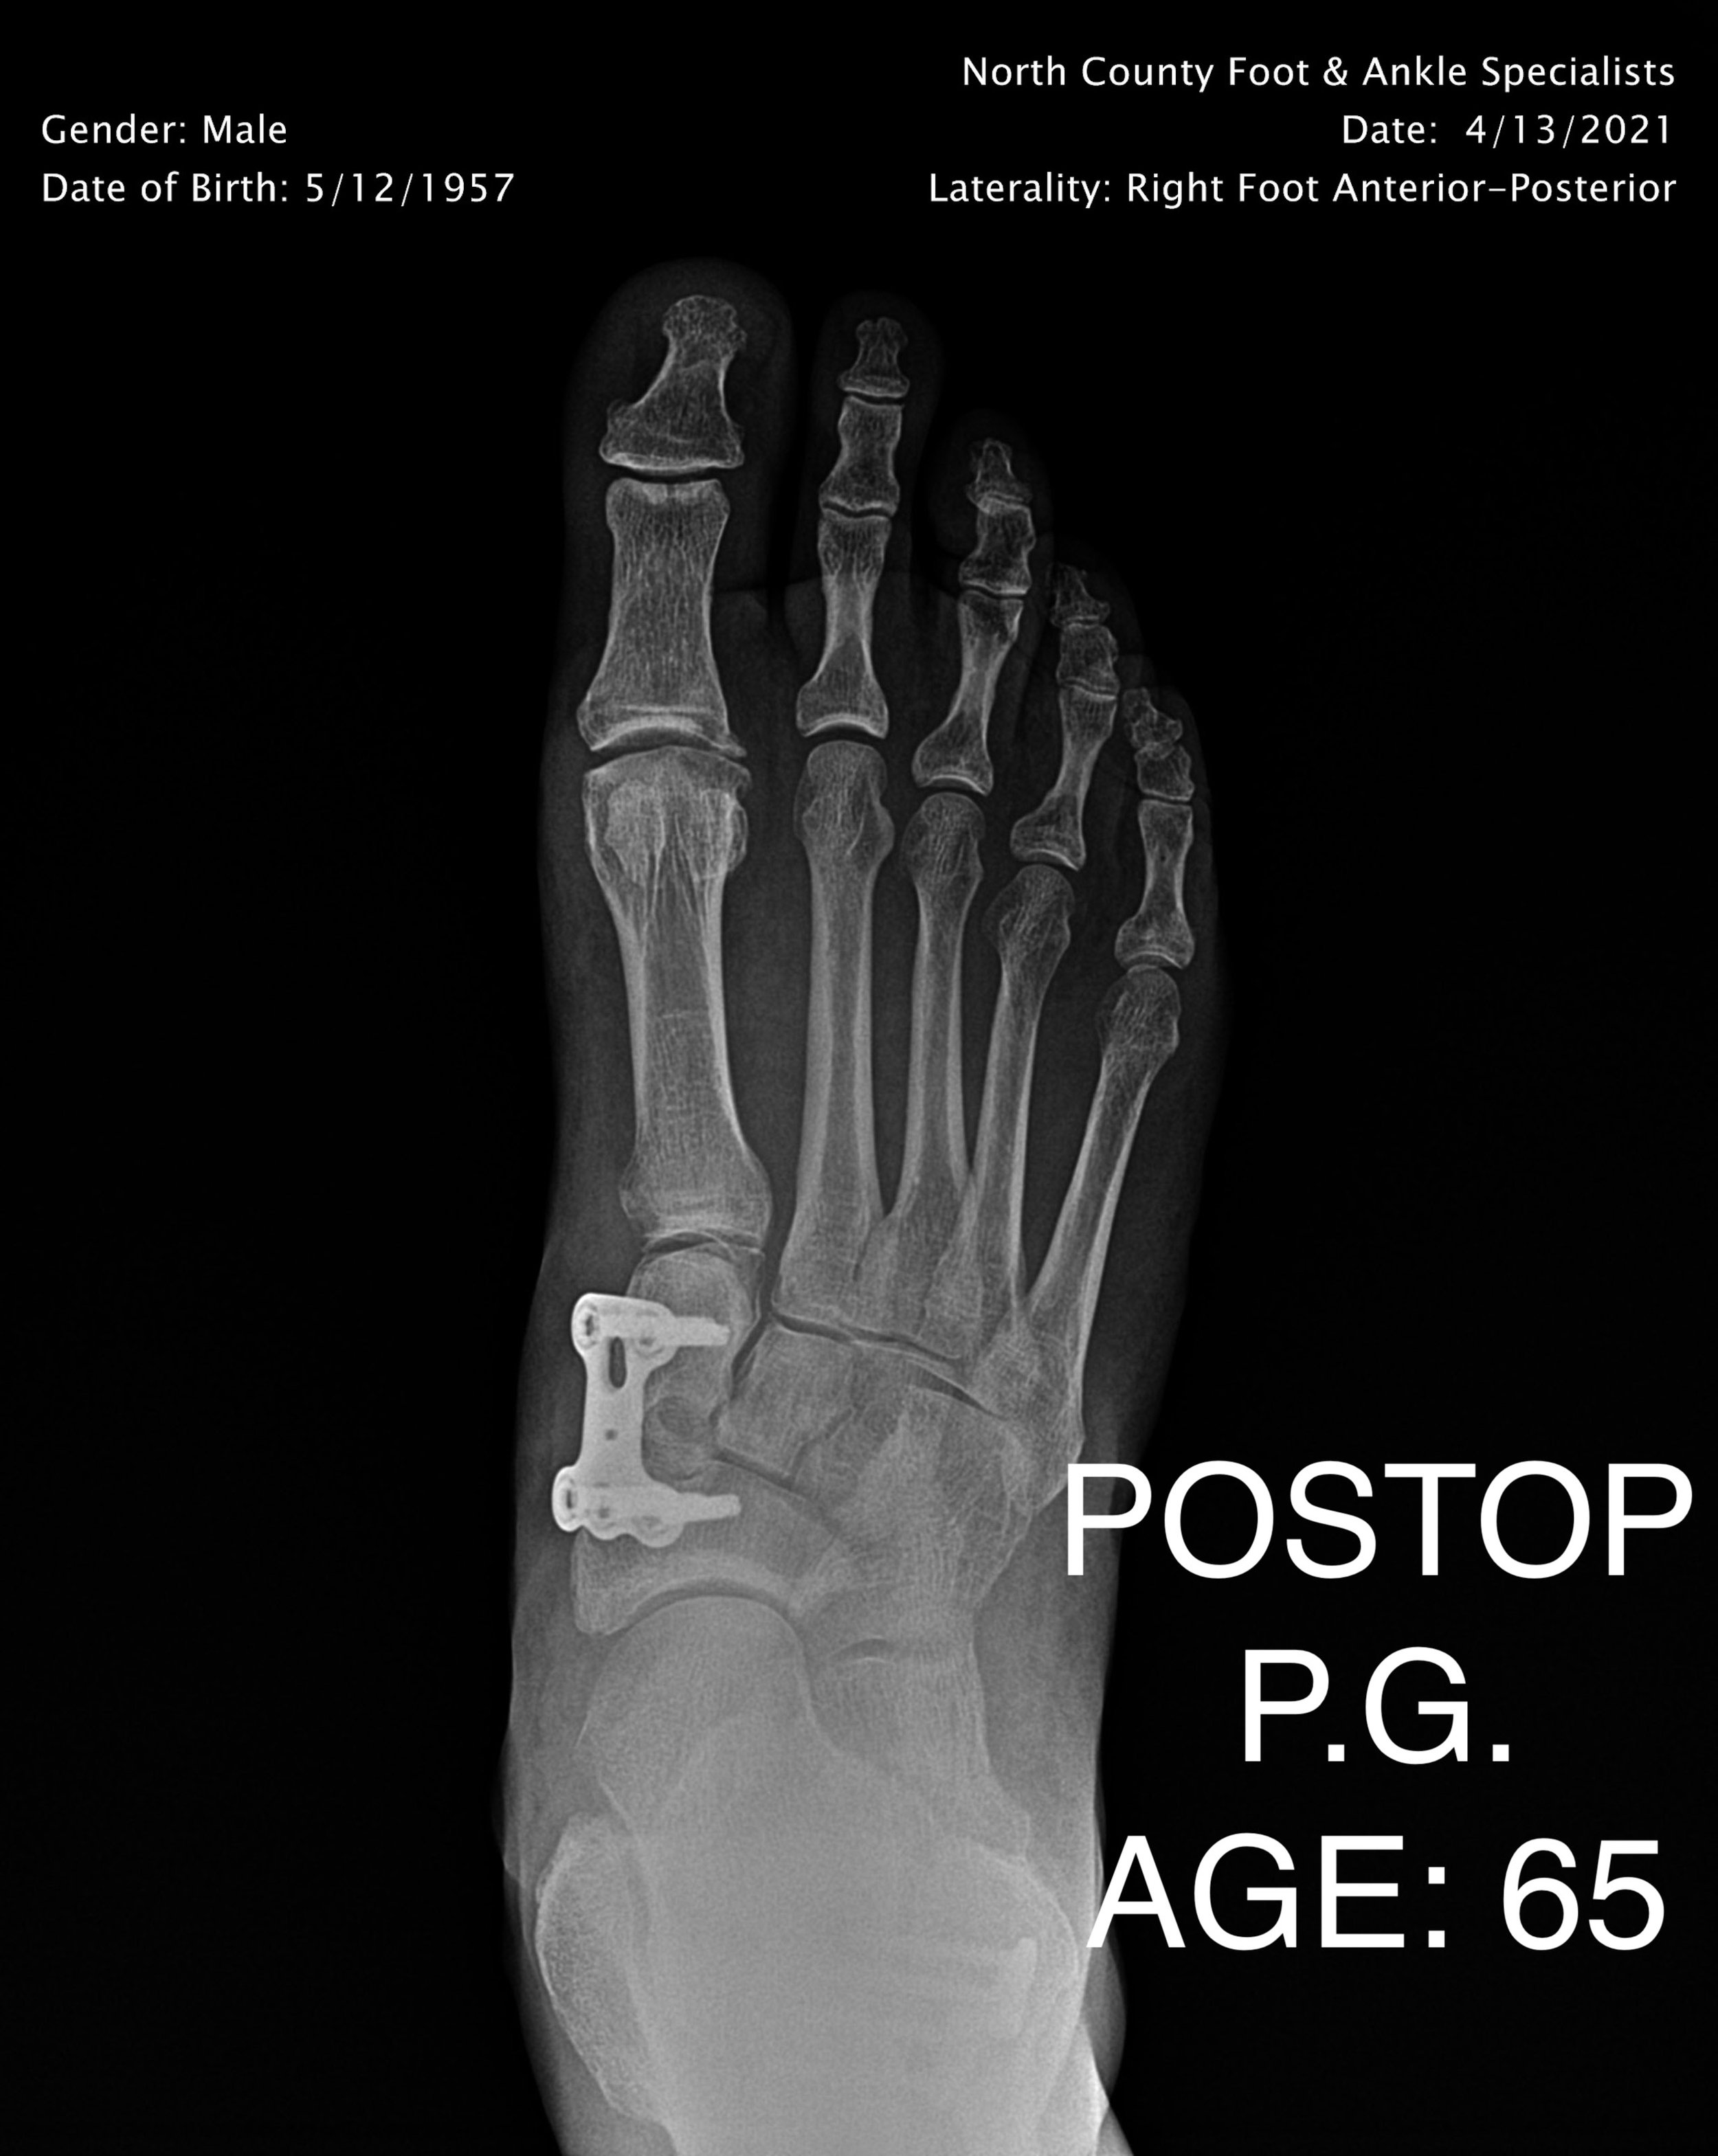

LAPIDUS